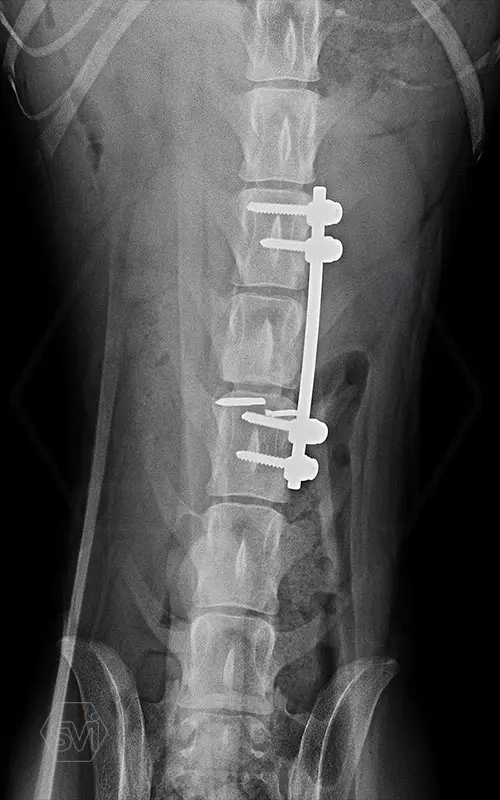

The best method to stabilize the spine is our patented SOP-LC system.

A gerinc stabilizálására a legjobb módszer a szabadalmaztatott SOP-LC rendszerünk.

Kutya neve: Benetton, az SOP-LC hatékonysága és stabilitása magáért beszél, a gyógyulás alatt a gerinc folyamatos terhelés alatt volt, és a fémek nem mozdultak el. A kutya szerencsére neurológiailag i felépült! Tehát van esély a gerinctörések esetén is a gyógyulásra...